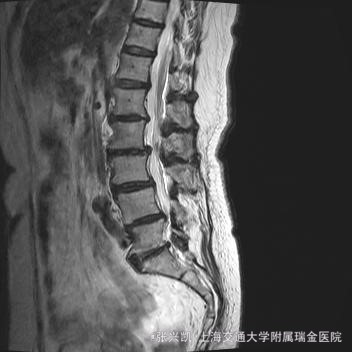

主诉:双下肢麻木7年,腰部酸痛无力 现病史:女性患者,70岁,患者诉腰背无力十几年,约于7年前无明显诱因下出现下肢麻木,站立位加重。后出现腰臀部僵硬,弓背加重,行走距离较短, 不足百米,几年前外院检查诊断为腰椎管狭窄,具体不详。

查体:侧弯畸形,右臀部及右下肢麻木疼痛,腰部活动受限,难以站立。右侧支腿抬高试验50°。双下肢肌力肌张力可。 辅助检查: 磁共振:L1-5,L5-S1腰椎椎间盘突出,腰椎退变,腰椎侧弯

诊断: 腰椎侧弯,腰椎间盘突出 治疗:1期微创侧路椎体融合术+2期 微创后路经皮内固定术